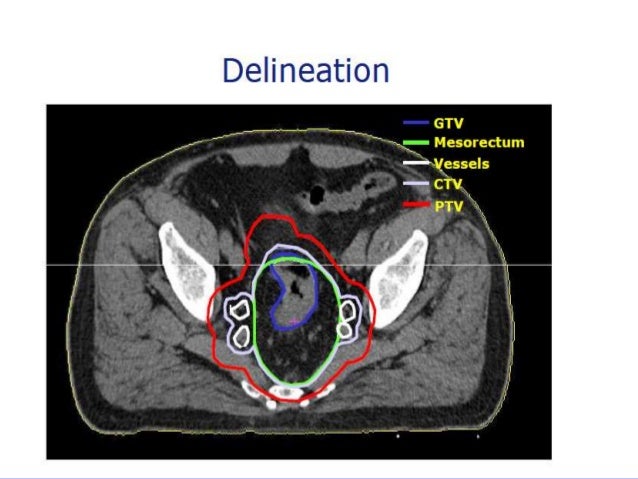

58. 58. 3-D Conformal RT ΢πλνιηθή δόζε 50.4 Gy ζε 28 ζπλεδξίεο • 45 Gy ζηελ πύειν ζε 25 ζπλεδξίεο πξελήο - 3 πεδία • 5.4 boost ζηνλ όγθν/κεζννξζό ζε 3 ζπλεδξίεο πιάγηα πεδία ή 3 πεδία • θεθαιέο κεξηαίωλ, ιεπηό έληεξν ≤ 45 Gy